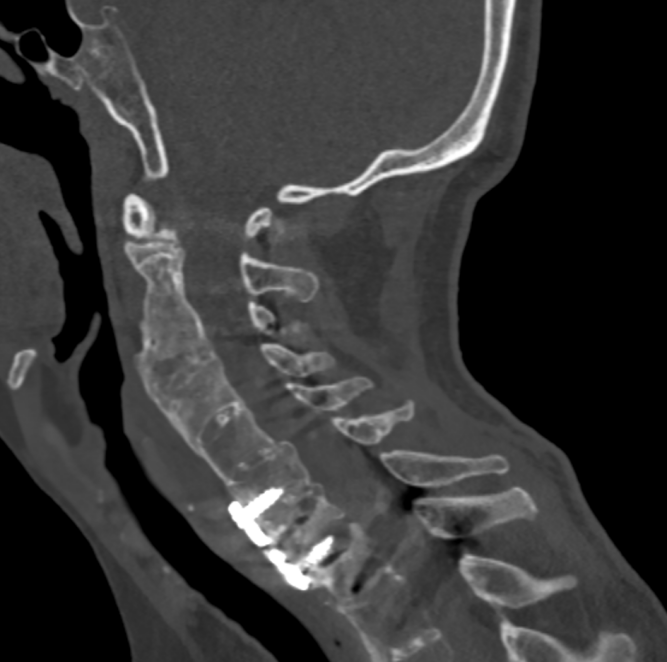

金先生伤后第7天,姜主任医师团队在麻醉手术科的密切配合下成功为他实施手术。姜主任凭借多年徒手置钉的过硬技术经验,2小时不到便完成了手术,术中出血仅100ml。术后CT显示齿状突完美复位,螺钉“不偏不倚”的位置恰到好处。术后,金先生在骨科护士长张霞芬护理团队的精心护理下,15天后伤口拆线康复出院。

第一步是先从颈椎后方入路,使用手术器械将骨折脱位复位,然后用螺钉固定;第二步是待患者恢复一段时间后再行前路手术。这个术式的难点在于强直性脊柱炎患者有严重的骨质增生表现,解剖标志不清,置钉有难度;其次,CT显示后方关节突交锁,复位困难。姜主任再次凭借多年手术经验,在二代0臂机的保驾护航下,成功地将螺钉置入椎体内,手术历经3小时。术后,金先生的右侧肢体偏瘫有了明显改善,2周后出院。

一个月后,金先生迎来了他的第二步的手术:颈前路植骨融合固定术。手术很顺利,1周后,金先生出院。出院前金先生的妻子王女士眼含热泪跟床位护士袒露心声:“我们很信赖姜主任和独墅湖医院骨科,是独墅湖医院给了我家先生两次生的机会。我们全家衷心感谢你们!”金先生也诚挚地向姜为民主任表达了自己的感激和敬意。王女士紧紧拉住前来探望的张霞芬护士长的手说道:“感谢姜主任救了我老公,拯救了我们这个家庭,感谢骨科全体医护人员对我们的照顾……”